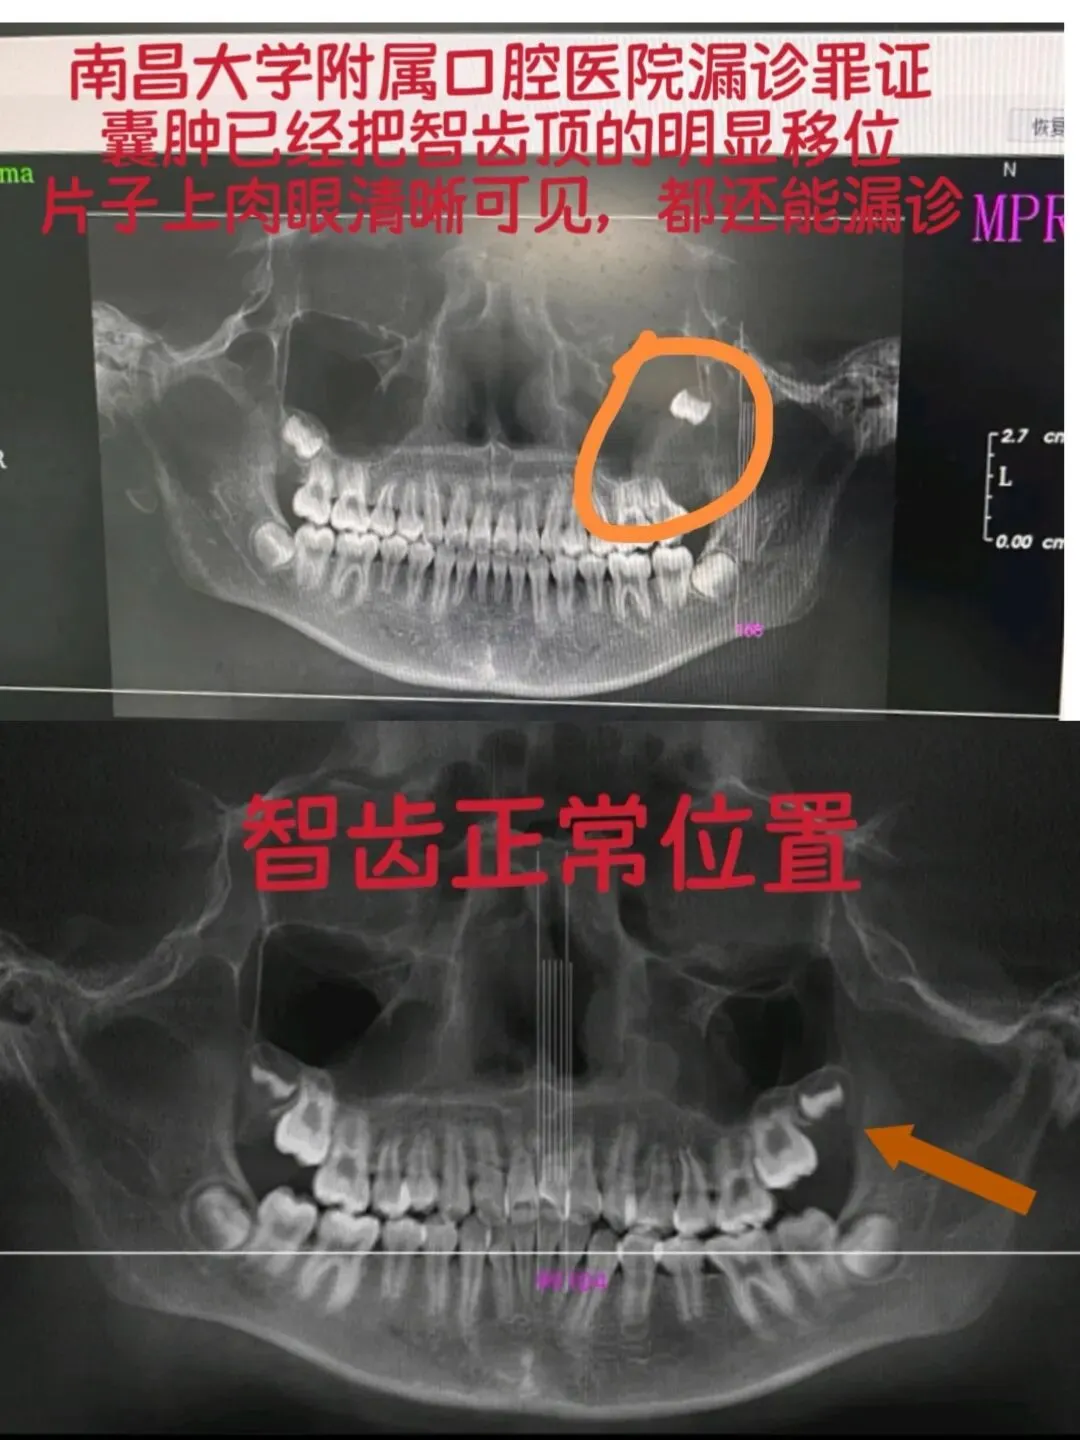

就因为这套无耻操作,我家孩子的骨性问题被当成牙性问题瞎治两年,囊肿在CT片上明明白白,愣是被漏诊!现在要做两次全麻手术,未来还要面临一场创伤极大的正颌手术!一个正在长身体的孩子,被他们的“免责算盘”害成这样!